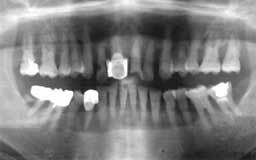

Nさん 初診時 51歳 女性

10年以上前からメインテナンスを受けていたということで、治療済みの歯や虫歯が多いもの の、歯周組織の状態は良好

Nさん 20年後 71歳

金属の被せが非常に目立ちますが、28本すべて健在は立派です